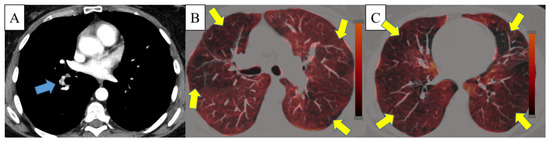

2.4. Analysis of Perfusion Defects

3.2.3. Assessment of Dual-Energy Iodine Maps